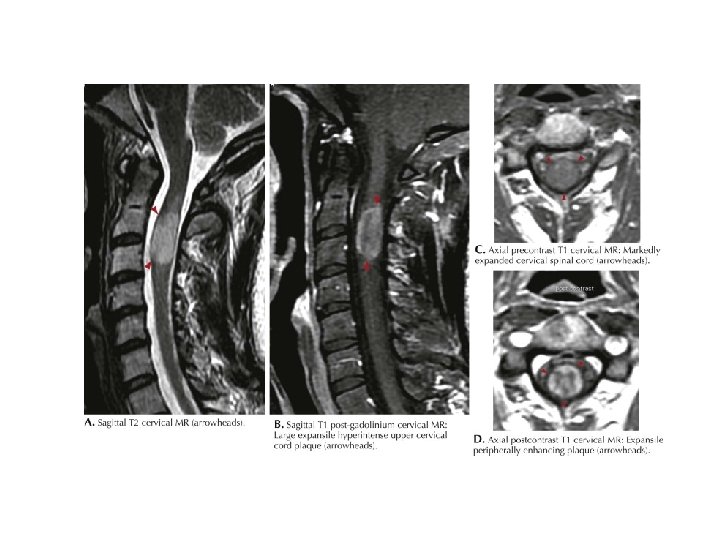

MRI BULGULARI • Periventriküler ak maddede plaklar • Serebellum / beyinsapı / servikal ve torakal spinal kord • Kontrast madde (Gadolinium) tutulumu aktif lezyon varlığını gösterir – Her zaman hastalık aktivitesinde artış ile korelasyon göstermez

MRI • MRI anormalliği: – Kesin MS’de %90 – Olası MS’de % 70

AK MADDE LEZYONLARI